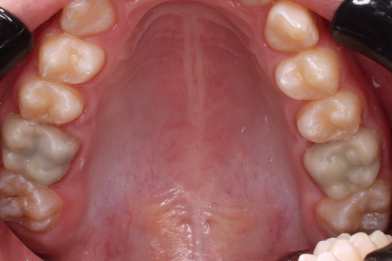

Жалобы на выпадение пломб. Произведено восстановление анатомо-физиологический формы

Бояринов Сергей Эдуардович

зубов при помощи пломбировочного материала. -